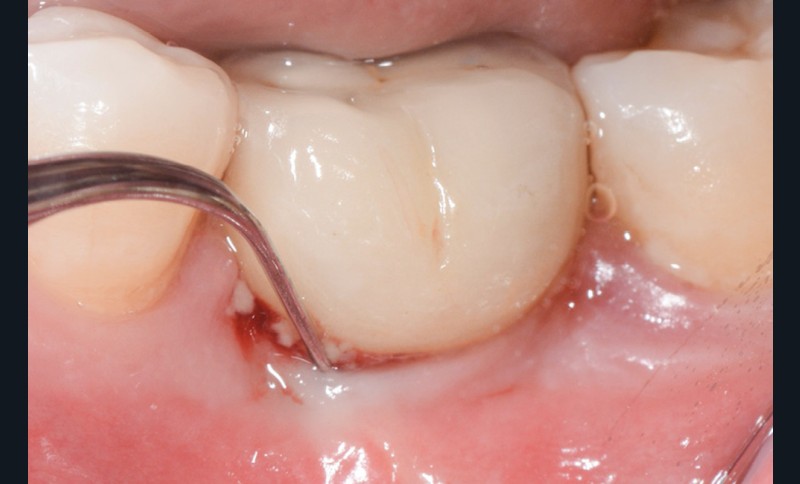

- Péri-implantite diagnostiquée en 2021

Chez ce patient, le traitement de la péri-implantite a comporté une chirurgie associant décontamination électrolytique de la surface implantaire, régénération osseuse guidée et enfouissement de l’implant. Le résultat à 2 ans est très moyen au vu du pourcentage de régénération osseuse obtenu. Comment peut-on prévoir un tel résultat alors que l’on a suivi les recommandations à la lettre, que l’on a utilisé les dernières technologies de décontamination, que l’on y a mis tous les moyens, que le patient est en bonne santé générale et qu’il vient en plus régulièrement aux séances de thérapeutique de soutien ? Le succès du traitement des péri-implantites n’est pas simple à obtenir, surtout quand un élément clé est compromis… la maintenance personnelle ! En effet le succès n’est possible que si le contrôle de plaque quotidien est optimal et, ici, ça n’était pas le cas. Le patient se brossait certes les dents, mais ne passait pas quotidiennement les brossettes, ce qui…